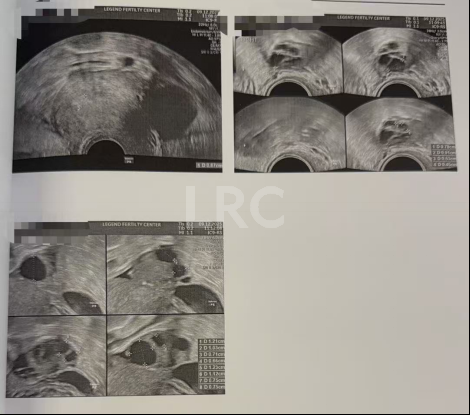

促排第五天

阴超检查(只数能用卵子):

- 右侧可用卵泡 3 颗(8,7,5mm)

- 左侧可用卵泡 5 颗 (13,12,12,10,9,9,7mm)

激素水平检查:

- 促黄体生成素 10.00 miu/ml

子宫内膜厚度:6.7mm

治疗结果

取卵及受精

取卵:9颗

成熟MII:6颗

ICSI受精成功:5颗

养囊成功:5颗

- 养囊率 100%